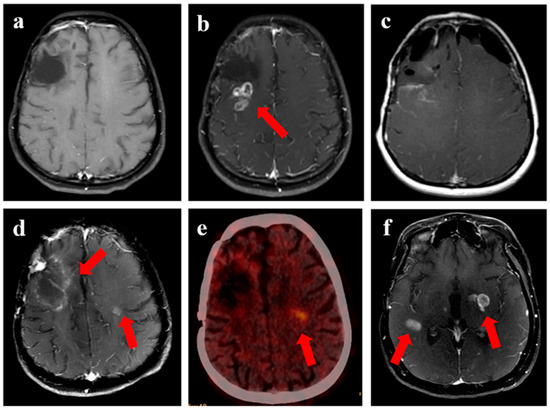

Figure 3.

Progression in a 47-year female with glioblastoma with MGMT gene promoter methylation. (a) shows T1w axial view following completion of adjuvant chemotherapy (after surgery and radiation), with (b) showing local recurrence after 2.5 years with enhancing component and cystic component (arrow). (c,d) represented the surgical cavity on T1w contrast and T2w FLAIR axial view when the patient was considered for reirradiation.

Figure 4.

Disease evolution from first progression to subsequent recurrence following re-irradiation in a 25-year female with IDH-mutant grade 3 astrocytoma. (a) shows T1w contrast-enhanced MRI with resection cavity over the right frontal region, with contrast-enhancing recurrent disease seen over the posterior aspect of the cavity (arrow) in (b). Subsequent imaging shows MRI following resection of the disease in (c), which was confirmed as recurrent HGG. (d) shows an enhancing area with central necrosis over the resected and re-irradiated region (8 months following ReRT) over the right frontal-parietal, which was not showing any metabolic uptake on corresponding PET imaging in (e). However, the other area of enhancing nodule over the left periventricular region shows high avidity, considered a distant recurrence. (f) shows MRI performed after 2 months, which confirmed new areas of distant disease, while the re-irradiated region (non-avid on PET) continued to be stable, confirming RT-related changes.